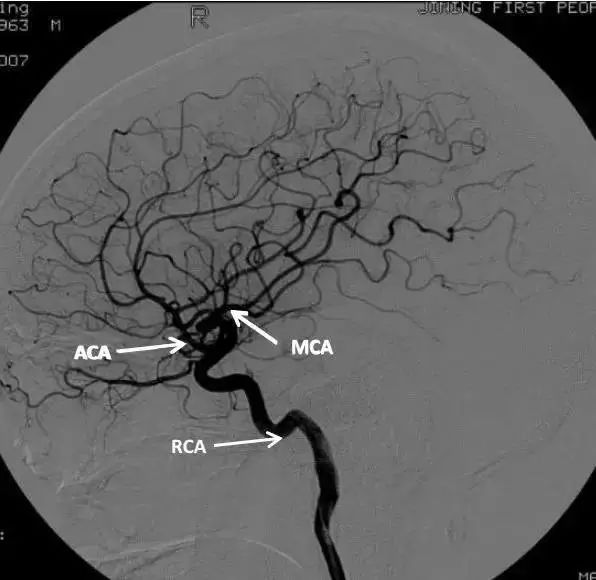

以下是颈内动脉、ACA和大脑中动脉的正、侧血管造影。

A1段,即水平段:起始后向前内经视交叉背面折入大脑纵裂至前交通动脉。正位片上呈由外向内水平走向或略呈弧形。侧位片上成轴位投影并与大脑中动脉重叠,显示不清。A1段上移常提示鞍区占位性病变,ACA在此段闭塞可不产生症状,因远端可以从前交通获得血液。如下图。